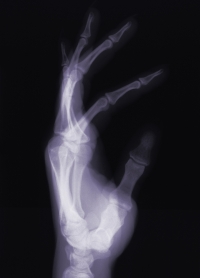

Csontdaganatra utaló tünet az érintett végtag deformitása, körülírt duzzanata vagy úgynevezett patológiás törése. Ez utóbbi során előzetes trauma nélkül jön létre a törés a daganat által meggyengített területen. Előfordul, hogy ez az első jele a betegségnek, és az ilyenkor szükséges röntgenvizsgálat során derül fény az elváltozásra.

Röntgenfelvételen megszakadhat az érintett csöves csontok úgynevezett kérgi részének folytonossága, a csonthártya felől új, esetleg réteges szerkezetű csont képződhet. A daganat környező szövetek felé való betörésének, pontos elhelyezkedésének, a környezet vele szembeni reakciójának és az előrehaladottság mértékének megítélésére további speciális, komputerizált radiológiai lehetőségek kínálkoznak (CT, NMR).